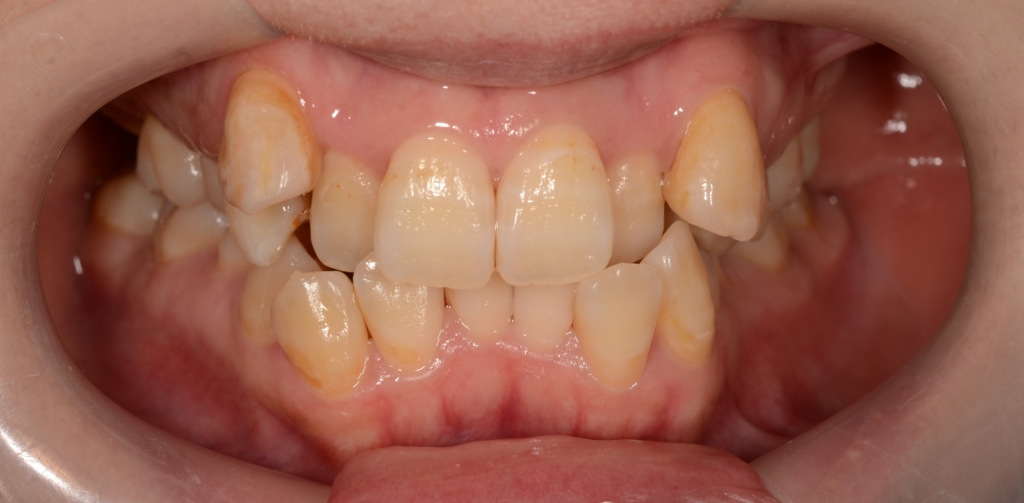

患者さんは、30代の女性(社会人)です。

「八重歯などのガタガタを治してきれいな歯並びになりたい!」

というのが一番の希望でした。

合わせて、口元が少しでも引っ込んで、お口を閉じる時にオトガイ辺りの「力」が抜けてしわが無くなればもっと嬉しい!とのことでした。

#1.顎と歯の不調和による叢生(重度)

#2.上顎前突(出っ歯)傾向

と診断しました。